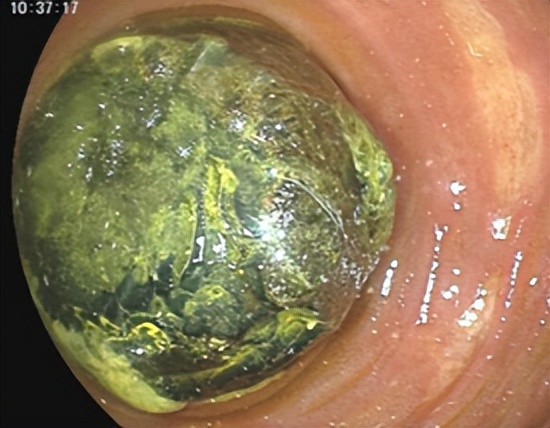

入院后经过详细检查,确诊患有十二指肠巨大结石,并阻塞肠腔形成梗阻。既往胃结石或胃结石移位至十二指肠内的患者,可通过口服碳酸氢钠注射液的方式使结石溶解或部分松解,再通过圈套器将结石碎成小块,患者可自行排出体外,但于爷爷的结石大且坚硬,应用上述办法内镜下碎石并不适用。(图2)

图2